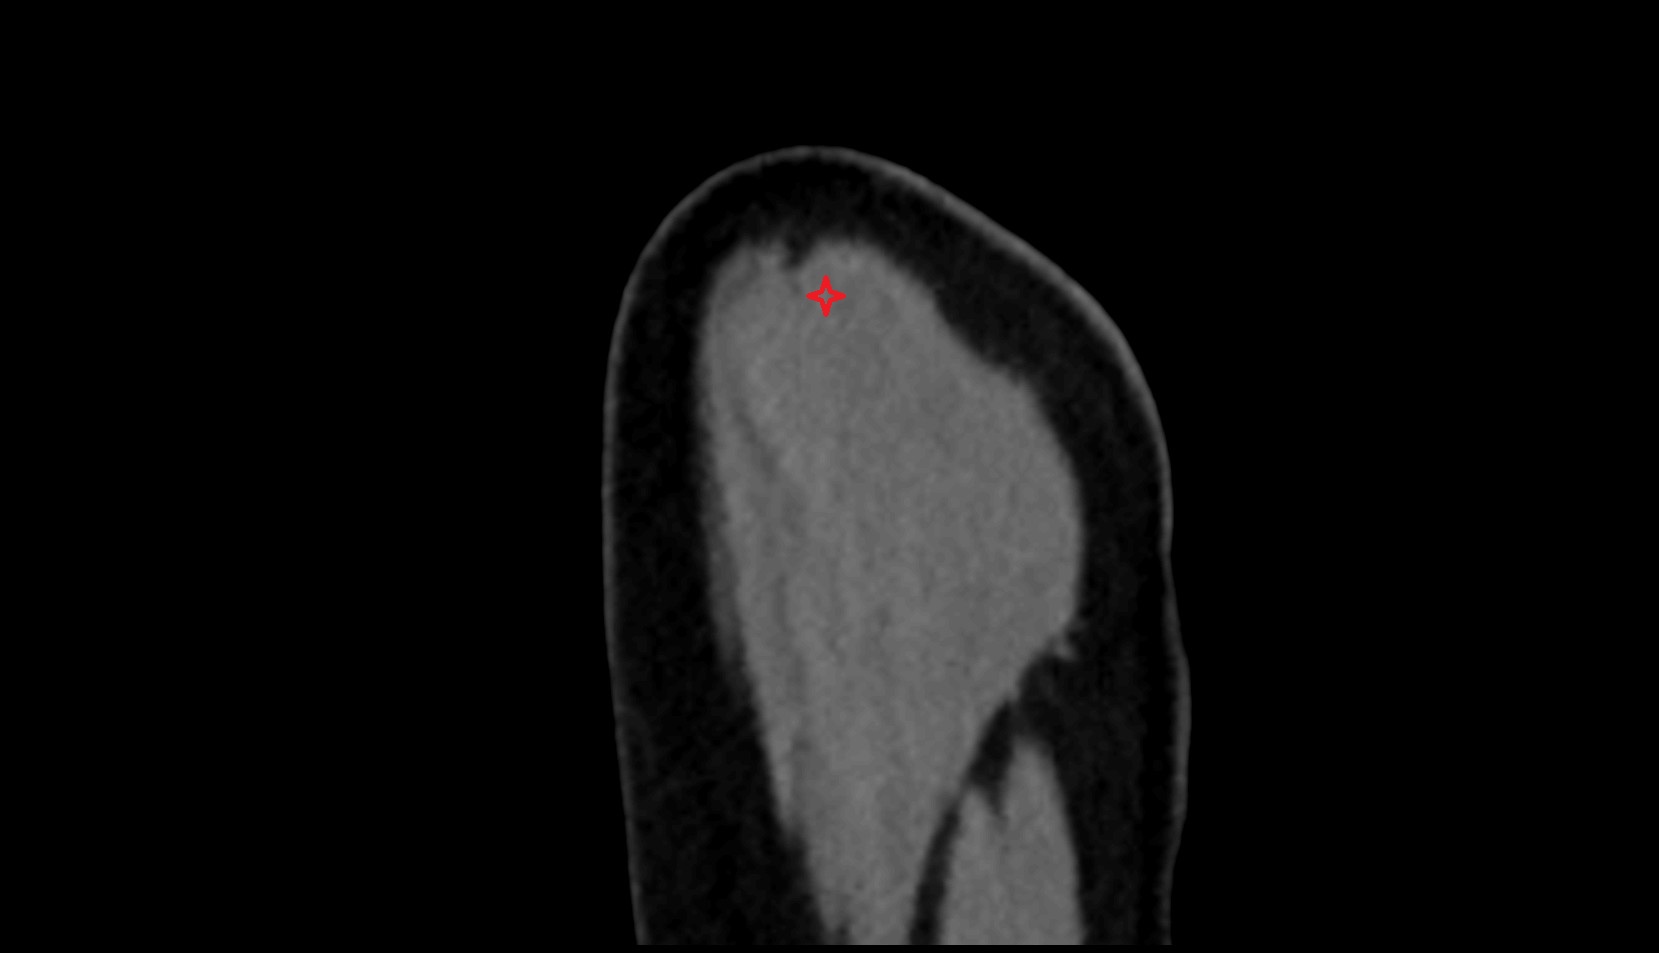

- Shoulder joint (glenohumeral joint)